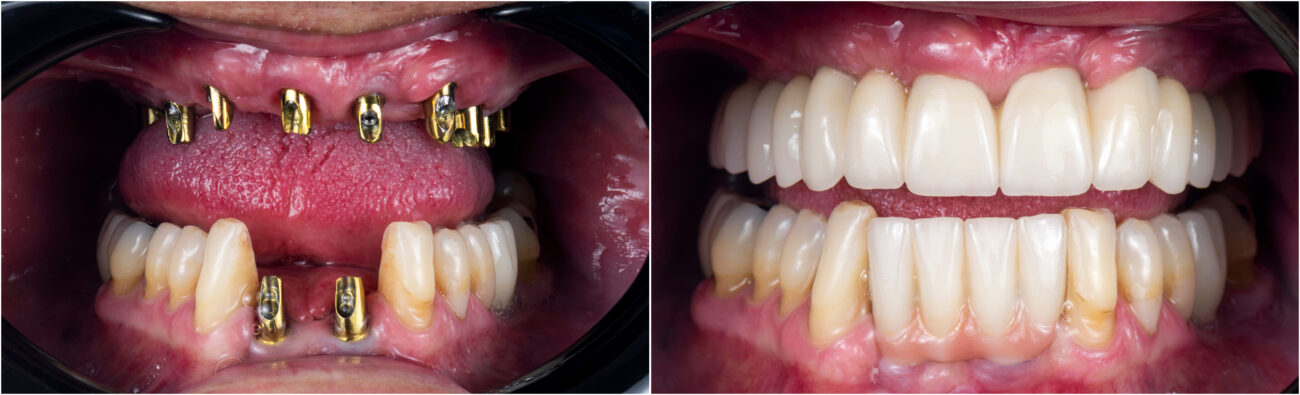

FIXED TEETH IN A WEEK

Using immediate implants, we can give you a complete new set of teeth in a week! No more waiting, no more long duration without teeth.

Immediate implant loading

Immediate implant loading requires functional occlusal loading of an implant within 48 hours of its insertion. In contrast to conventional loading, immediate loading considerably reduces the waiting period between implant insertion and loading, as well as the number of visits to the dentist. The assumption is that an initial primary stability can be achieved in the old bone and will change over time into secondary stability in new and osseointegrated bone.